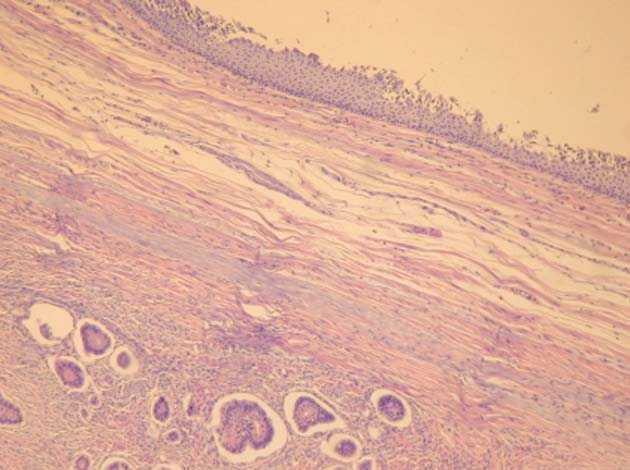

En el estudio microscópico de la zona sólida (fig. 3) encontramos una neoformación epitelial con claros carácteres «insulares». Los grupos neoformativos se disponen en islotes de tamaño medio y pequeños muy bien definidos, con celularidad redondeada con núcleos hipercromáticos, isonucleosis, isocariosis y escasa mitosis. Estos islotes presentan luces alrededor de las cuales se distribuyen en forma de empalizada de células cuboidales o cilíndricas. En otras zonas, la neoformación adopta una disposición glanduloide, mezclada con el tejido insular descrito que muestra en esta zona criterios de atipia nuclear y celular más acentuada (fig. 4).

Figura 3.1) En la parte superior se observa un margen de epitelio escamoso bien diferenciado, que corresponde a la pared quística del teratoma. 2) En el ángulo inferior izquierdo se aprecian islotes de la neoformación carcinoide (HE, ×40).